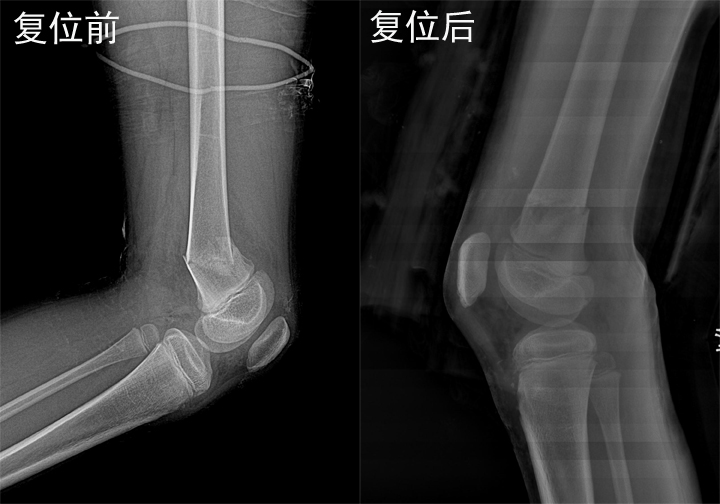

梁氏正骨-梁俊超正骨案例